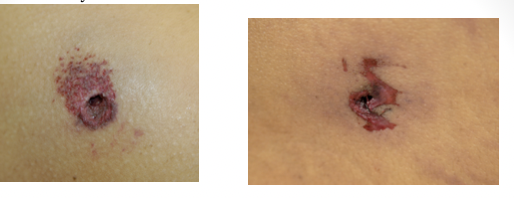

circular defect with marginal abrasion

inverted margins

soot and stippling

entrance wounds

contact gunshot wound

circular and smaller

stellate over scalp

burning /blackening of immediate wound edges

soot within tissues

muzzle mark

inverted wound margins

back spatter = blood sucked up into the barrel of the weapon